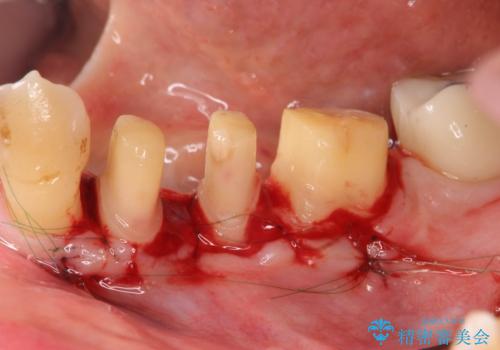

がたつきの強い天然歯を矯正治療で整えたのち、再生治療、歯周ポケットを除去する歯周外科手術を行いました。

歯周病の問題が解決したのち、歯の揺れを抑えるべくセラミッククラウンで連結補綴をおこなっています。

再生療法を行ったことで、抜歯をされてもおかしくなかった歯を、残すことができました。